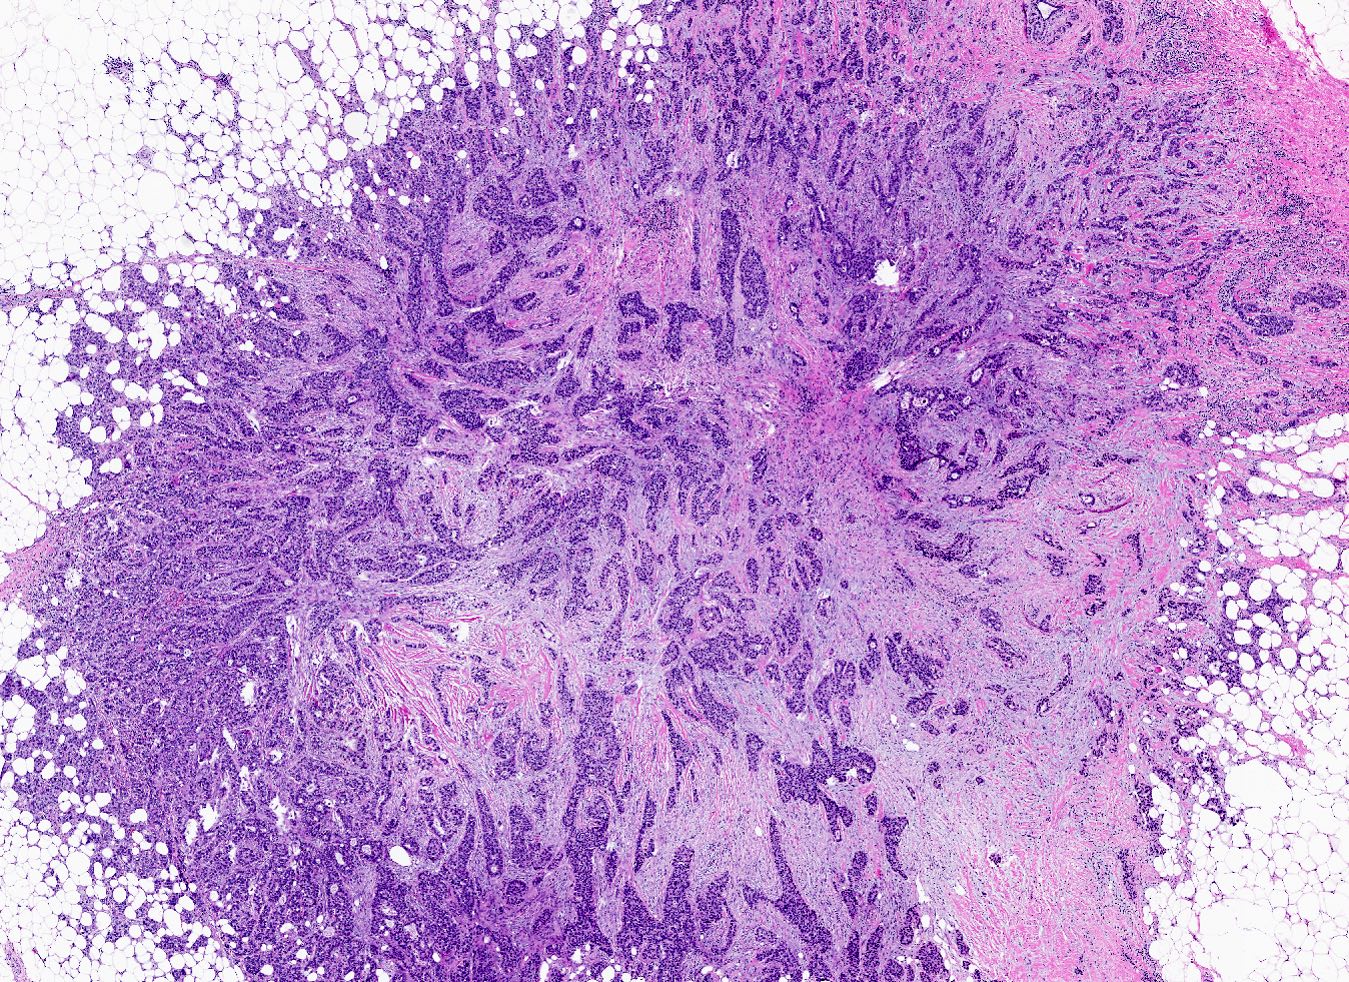

- Triple negative (J Pathol 2008;216:141, Breast Care (Basel) 2020;15:327, Semin Cancer Biol 2021;72:136)

- ER negative, PR negative, HER2 negative, includes high and low grade tumors

- High grade TNBC: IDC, NST grade 3, spindle cell metaplastic breast carcinoma, medullary carcinoma, apocrine carcinoma

- Low grade TNBC: salivary gland-like tumors (secretory carcinoma, adenoid cystic carcinoma, acinic cell carcinoma, mucoepidermoid carcinoma), tall cell carcinoma with reverse polarity, low grade metaplastic carcinomas (adenosquamous carcinoma, low grade fibromatosis-like metaplastic carcinoma)

- Broken down into basal-like type 1, basal-like type 2, mesenchymal and luminal androgen receptor

- Debated distinct subtypes include immunomodulatory (IM) (high rates of tumor infiltrating lymphocytes [TILs]) and mesenchymal stem-like (MSL) (high levels of tumor associated mesenchymal tissue)

- Immunomodulatory and mesenchymal stem-like characteristics that may be present in different degrees of all TNBC subtypes

- Basal-like: high grade IDC, NST, solid tumor growth with pushing borders, geographic necrosis, nuclear pleomorphism, brisk inflammatory infiltrate, high mitotic index, high Ki67

- Most express basal cytokeratins (keratin 5/6, 14, 17) and EGFR

- HER2 enriched

- Predominantly IDC, NST of high histological grade

- Tumor cells frequently have pleomorphic nuclei and more abundant eosinophilic cytoplasm than triple negative cancers

- Ki67 proliferative rate is high (20 - 60%)

- Frequently associated with high grade comedo ductal carcinoma in situ

- Some pleomorphic invasive lobular carcinoma are HER2 positive

A 67 year old woman underwent a partial mastectomy for a breast tumor shown in the image. Microscopic sections revealed a high grade invasive ductal carcinoma growing as a solid mass with pushing borders, areas of necrosis, brisk mitoses and abundant tumor infiltrating lymphocytes. The tumor was negative for ER, PR and HER2 and was classified as basal-like by gene expression profiling. What other immunostain(s) might be positive?

B. EGFR. Basal-like breast cancers are typically high grade invasive ductal carcinoma of no special type that show solid tumor growth with pushing borders, geographic necrosis, nuclear pleomorphism, a brisk inflammatory infiltrate, a high mitotic index and a high proliferative index with Ki67. Most basal-like breast cancers express basal cytokeratins (keratin 5/6, 14, 17) and EGFR. Answer A is incorrect because while a minor proportion of triple negative breast cancers can express androgen receptor, the prototypical AR positive breast tumor has apocrine features (apocrine carcinoma). Answer C is incorrect because KIT is not characteristically expressed in breast carcinomas. Answer D is incorrect because synaptophysin may be expressed in breast tumors with neuroendocrine differentiation, which typically cluster within the luminal category.